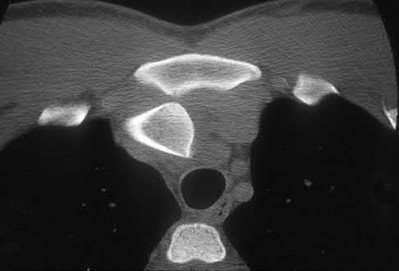

Which of the following images shows an injury pattern most consistent with a lateral compression type 3 pelvic ring injury?

Figure C is an axial CT scan of a lateral compression type 3 (LC3) pelvic ring injury.

Classically, LC3 injuries demonstrate an ipsilateral lateral compression and a contralateral APC (windswept pelvis) fracture pattern. The most common mechanism of injury in these cases is a rollover MVC or pedestrian vs. auto. LC1 injuries are characterized by an oblique or transverse ramus fracture and ipsilateral anterior sacral ala compression fracture, while LC2 injuries consist of a rami fracture and ipsilateral posterior ilium fracture dislocation (crescent fracture). While LC1 injuries can often initially be managed conservatively with protected weight-bearing and close observation, LC2 and LC3 pelvic ring injuries are almost universally operative.

Pennal et al. discuss a radiologic technique for assessing the forces producing pelvic disruption and its use in logically classifying pelvic injury. Based on this radiologic assessment and along with some biomechanical studies, they propose a classification system involving three major forces producing injury that can also be helpful in the management of these patients.

Young et al. performed a retrospective analysis of the plain radiographs of 142 cases of pelvic fractures and identified four patterns of force that presented with distinctive, recognizable radiographic appearances. They describe a classification system for pelvic fractures based on radiographic and clinical findings that correlates with associated injury to soft-tissue structures and enables the surgeon to begin corrective procedures rapidly.

Incorrect Answers:

Answer 1: This represents a lateral compression type 2 injury. Answer 2: This represents a lateral compression type 1 injury.

Answer 4: This represents an anterior posterior compression type 2 injury. Answer 5: This represents an anterior posterior compression type 3 injury.